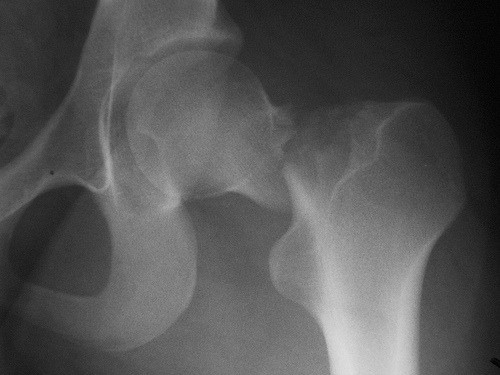

Un análisis de los pacientes del estudio ALLHAT muestra reducción de fracturas de cadera y pelvis durante el tratamiento con clortalidona en comparación con amlodipina o lisinopril. JAMA Internal Medicine, 21 de noviembre de 2016